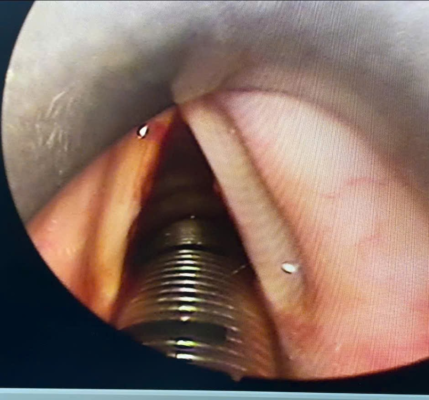

Hình 3:  Hạt xơ dây thanh 2 bên

• Hạt xơ dây thanh thường xảy ra hai bên ở 1/3 giữa dây thanh. Nguyên nhân chính của chúng là lạm dụng giọng nói mãn tính: la hét, la lớn, hát to, hoặc sử dụng một tần số thấp không tự nhiên.